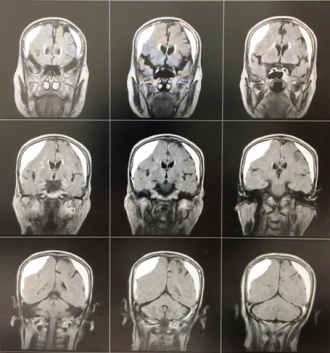

すぐに頭部MRIを施行して、小さい脳梗塞と診断しました。

症状は軽いですが進行しており、治療が必要と判断し救急外来に紹介しました。2週間ほど入院して治療し、症状は改善したようです。